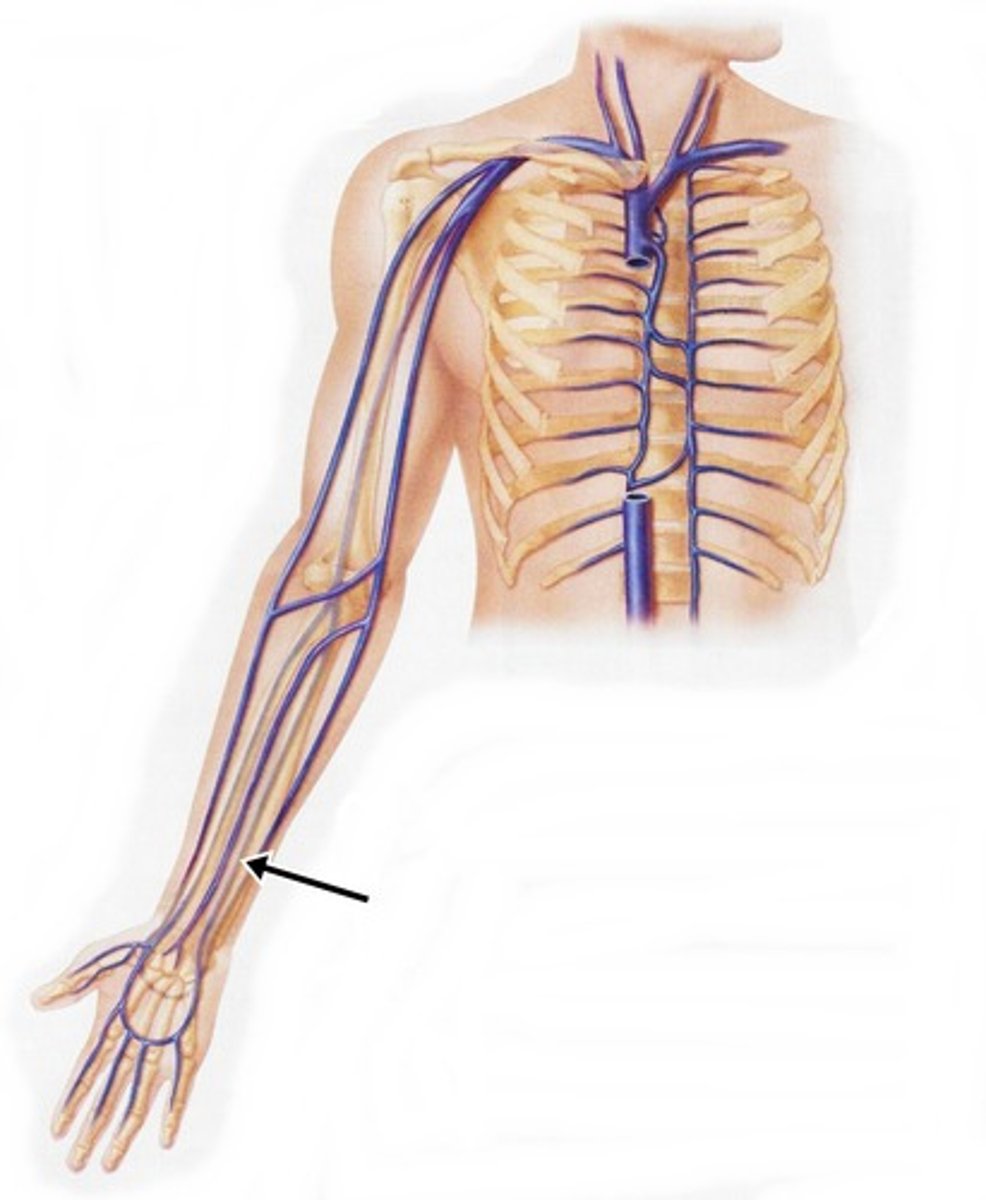

brachial vein

cephalic vein

radial vein

ulnar vein

subclavian vein

axillary vein